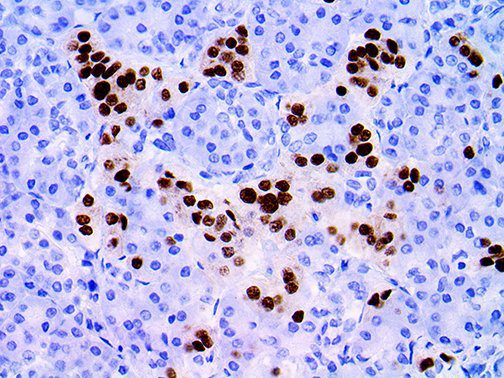

It is the ICU physician who is most likely to witness one of the deadliest manifestations of the abnormal immunological response, the cytokine storm syndrome (CSS). This response is also referred to by some as the cytokine release syndrome (CRS). CSS is characterized by continuous activation and expansion of macrophage and lymphocyte populations, which secrete large amounts of cytokines, causing the cytokine storm. This massive cytokine release is akin to hemophagocytic lymphohistiocytosis (HLH) disease, a syndrome characterized by initial unchecked and persistent activation of cytotoxic T lymphocytes and NK cells.

Clinical and laboratory manifestations of HLH include fever, enlarged liver and/or spleen, neurologic dysfunction, coagulopathy, liver dysfunction, cytopenias (i.e., low levels of erythrocytes, leukocytes, and/or platelets), hypertriglyceridemia, hyperferritinemia, hemophagocytosis, and eventually diminished NK cell activity as the immune system becomes progressively paralyzed. HLH can be familial (primary HLH) or secondary to another disease process (sHLH), such as rheumatic disease, in which it is referred to as macrophage activation syndrome (MAS, characterized by elevated ferritin).